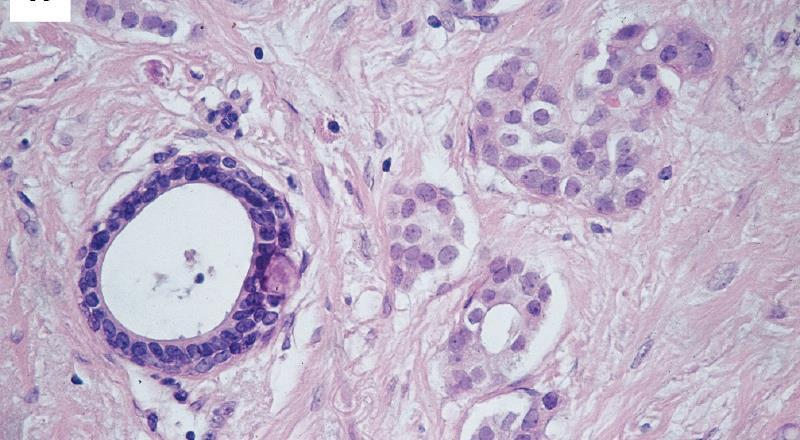

All parts of the tumour are scanned. Clear acinar or gland formation or defined tubular structures with a central luminal space are assessed semi-quantitatively.

Score 1

Score 2

Score 3

1: Nuclei small in size with little increase in size in comparison with normal breast epithelial cells, regular outlines, uniform nuclear chromatin. 2: Cells larger, open vesicular nuclei, visible nucleoli, moderate variation in both size and shape. 3: Vesicular nuclei, prominent nucleoli, marked variation, large bizzare forms.

5-14% of breast carcinomas High incidence of multifocal and bilateral disease Tumour cells may show mucin filled vacuoles E-cadherin negative

E-cadherin